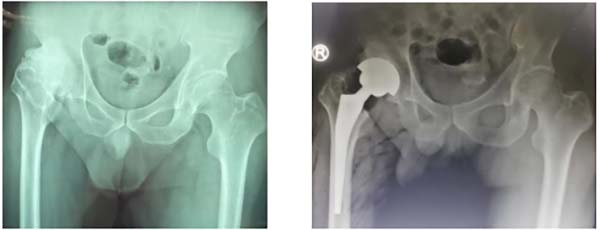

PART.2人工全髋关节置换术

人工全髋关节置换术主要目的是缓解疼痛、矫正畸形、恢复和改善关节功能,主要适应症为髋骨关节炎、股骨头坏死、股骨颈骨折、发育性髋关节发育不良(DDH)、髋部肿瘤等。科室熟练、高质量开展髋膝关节置换术、Crowe分型三、四型DDH及复杂股骨头坏死手术,成功解决患者髋痛顽疾,恢复正常步态行走。